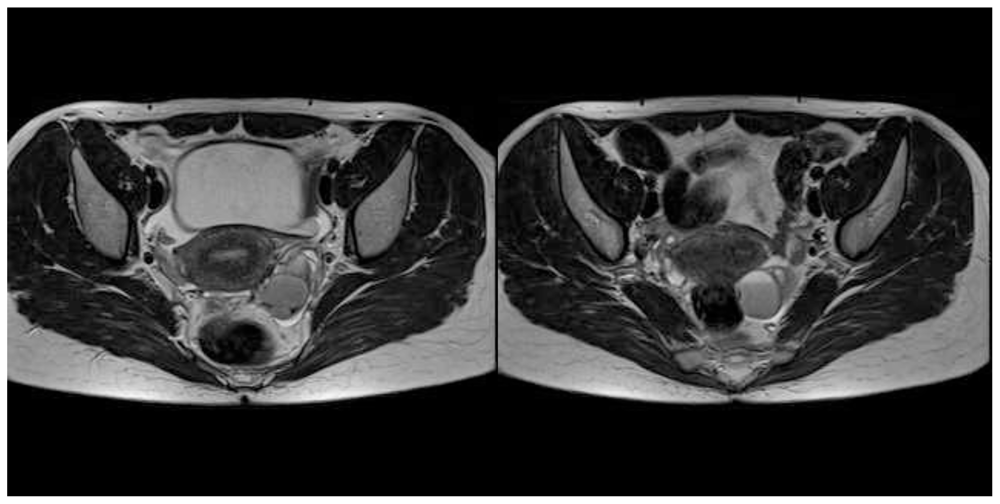

2. Case Presentation and Discussion